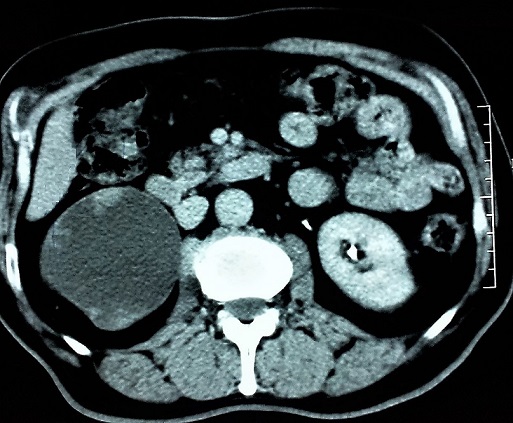

L'association tumeur de la voie excrétrice supérieure et hydronéphrose due à un syndrome de la jonction pyélo-urétérale est une entité rare. En effet, les tumeurs de la voie excrétrice supérieure et l'hydronéphrose ont classiquement une relation de cause à effet. Cette dernière est due le plus souvent à l'obstruction par une tumeur de l'uretère ou de la jonction pyélo-urétérale. Nous rapportons le cas d'un patient de 66 ans, aux antécédents de tabagisme et de pyélonéphrite droite, présentant des douleurs lombaires droites évoluant par intermittence depuis plusieurs mois sans hématurie. L'échographie a montré une dilatation des cavités pyélo-caliciels avec réduction majeur de l'index cortico-médullaire du rein droit. L'uroscanner a douté entre une dysplasie kystique du rein droit, et une hydronéphrose droite sur syndrome de la jonction pyélo-urétérale avec des images bourgeonnantes intra rénales faisant suspecter une tumeur pyélique. Le bilan a été complété par une cytologie urinaire quie est revenue positive. Une néphro-urétérectomie droite par laparotomie a été réalisé et l'examen anatomopathologique a confirmé qu'il s'agit bien d'un carcinome urothélial des voies excrétrices supérieures.